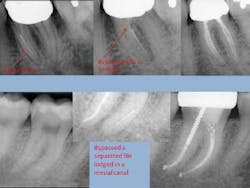

- Separated file — The dreaded separated file is probably the most common complication clinicians encounter when performing root canals. There was a time when those broken instruments made me wish I never started the root canal in the first place. These days, I will work to bypass the file and get a predictable result.

To prevent file fractures, irrigate after every file. Also, apply gentle pressure and never push when instrumenting a canal.

If a file separates, take a P.A. film immediately to figure out where in the canal the file is lodged. Most likely there’s a curve that the file could not negotiate. Start negotiating the canal with a 6 or 8 C-file. The goal is to engage the space around the file where you can instrument next to it. It could take an extra 30 or 40 minutes and lots of irrigation, but you should be able to negotiate the canal with a 15 file to working length. Irrigate very well and obturate. Sometimes the file will actually exit the orifice of the tooth when irrigating. But it’s perfectly reasonable to use the file as part of the fill.